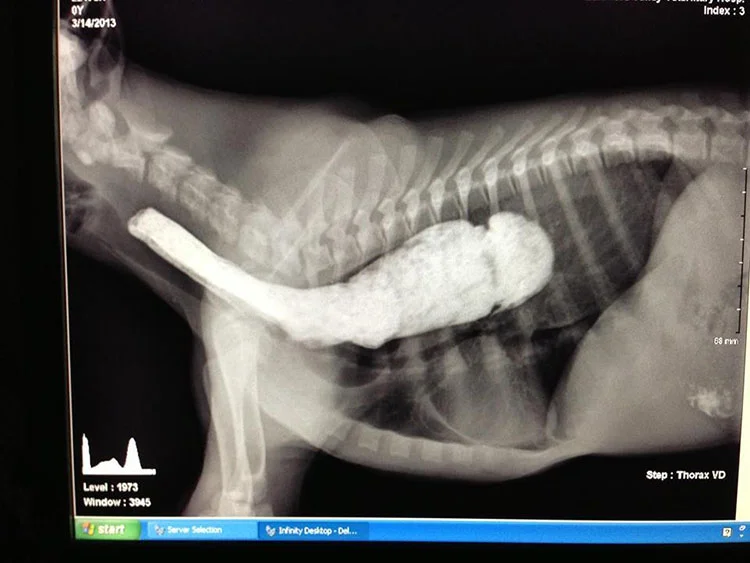

El esófago del animal crece demasiado grande, hasta el punto en que pierde la capacidad de contraer sus músculos, haciendo que la comida y los líquidos no puedan llegar al estómago.

A Chuck lo llevaron al veterinario y muy pronto fue diagnosticado con la extraña condición, y aunque los veterinarios dijeron que podrían operarlo e introducir una sonda para alimentarlo, Zaleski prefirió optar por una solución más natural.